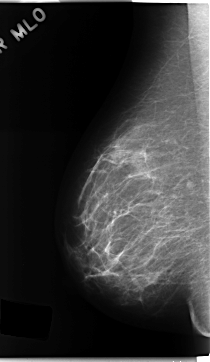

C_0161_1.RIGHT_MLO

RIGHT_CC LINES 4712 PIXELS_PER_LINE 2848 BITS_PER_PIXEL 12 RESOLUTION 50 NON_OVERLAY

RIGHT_MLO LINES 4704 PIXELS_PER_LINE 2728 BITS_PER_PIXEL 12 RESOLUTION 50 NON_OVERLAY